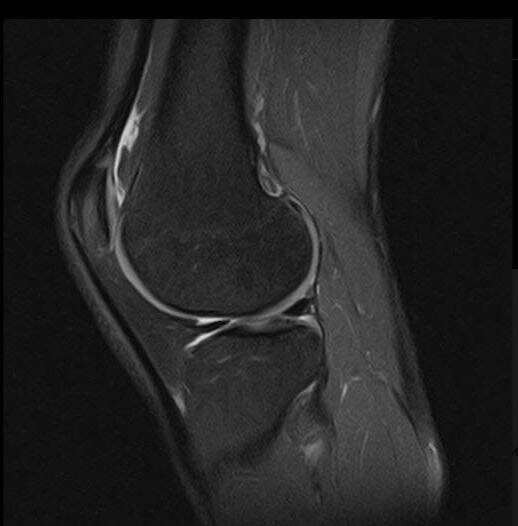

МРТ коленного сустава-когда нужно и зачем?

Коленный сустав-один из самых нагружаемых в нашем теле. Боль, хруст, отёк или ограничение подвижности-повод не терпеть, а разобраться в причине. Один из самых информативных методов-МРТ Что показывает МРТ?

Коленный сустав-один из самых нагружаемых в нашем теле. Боль, хруст, отёк или ограничение подвижности-повод не терпеть, а разобраться в причине. Один из самых информативных методов-МРТ

МРТ коленного сустава

Когда назначают МРТ:

-боли в колене без явной причины

-после травм и падений

-при подозрении на артроз, артрит или разрывы связок если лечение не даёт ре

зультата

Важно: МРТ не использует рентгеновское излучение и безопасно даже при частом проведении.

Чем раньше поставлен точный диагноз-тем быстрее и эффективнее лечение.